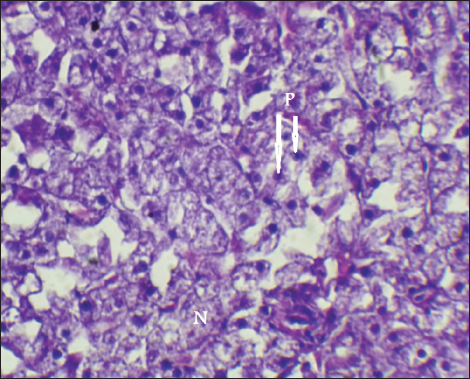

The result of histopathological alteration of the liver revealed degenerative and necrotic changes in liver tissue distinguished by pyknosis with the existence of necrosis in cells (Figs. 14 and 15) also, the result revealed dilation of the sinusoids with cytoplasmic vacuolation (Fig. 16).

Fig. 14. Histopathological sections of liver of C. carpio showing necrosis(N) and Pyknosis (P) (H&E X40).

This study showed that C. carpio contains different concentrations of the selected heavy metals in the liver, gill, and muscle, the causes of this differences is due to the collection of samples at different intervals and, therefore, the level of contamination in water and food and sediment varies depending on the time period also differences in fish’s internal uptake and water temperature. Kalay et al. (1999) revealed that the amounts of minerals that different fish species accumulate in their tissues vary noticeably. Furthermore, Canli and Atli (2003) revealed that heavy metals levels in fish vary between species and different aquatic environments. Conversely, Farkas et al. (2000) linked variations in mineral concentrations among fish to their feeding habits, the ability of each species to bioconcentrate, and the mineral’s biochemical characteristics. Roméo et al. (1999) also state that the environment, metabolism, needs, level of contamination in water, sediment, and food, as well as water temperature and salinity, all affect a fish’s ability to accumulate heavy metals. Also, Brraich and Kaur (2017) revealed that the levels of heavy metals in different fish organs are directly impacted by the contaminating of the aquatic environment and by the fish’s internal uptake, control, and removal of heavy metals.

It is well known that exposure to heavy metals can cause a variety of histopathological changes (Mustafa et al., 2012). These changes may be related to the harmful effects of heavy metals on hepatocytes, as the liver is involved in the biotransformation and detoxification of various pollutants and toxicants (Arellano et al., 1999). The observed necrosis in certain areas of the liver tissue may have been caused by the fish’s overwork in eliminating the toxins from its body during the detoxification process; this observation is consistent with the findings of Rhaman et al. (2002).